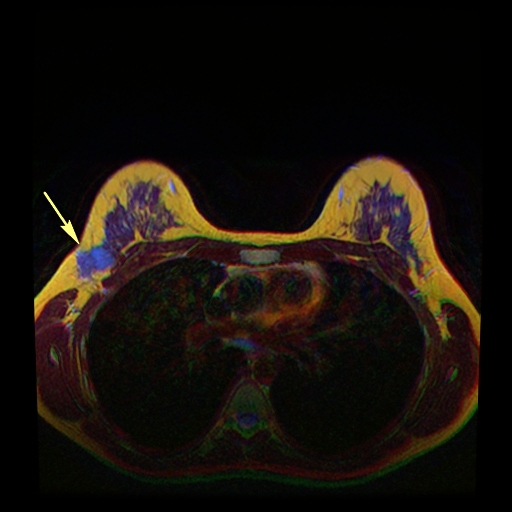

Invasive ductal carcinoma (IDC) develops when duct lining cells transform and spread into surrounding breast tissue.

Invasive ductal carcinoma (IDC) is the most common type of breast cancer.

Invasive ductal carcinoma (IDC) may by detected by physical examination or mammography.

Mammographically identified masses are often 1.0 cm or greater, while masses found by physical exam are typically 2.0 cm or greater.

Histology of invasive ductal carcinoma shows haphazard ductal cells in a desmoplastic stroma.